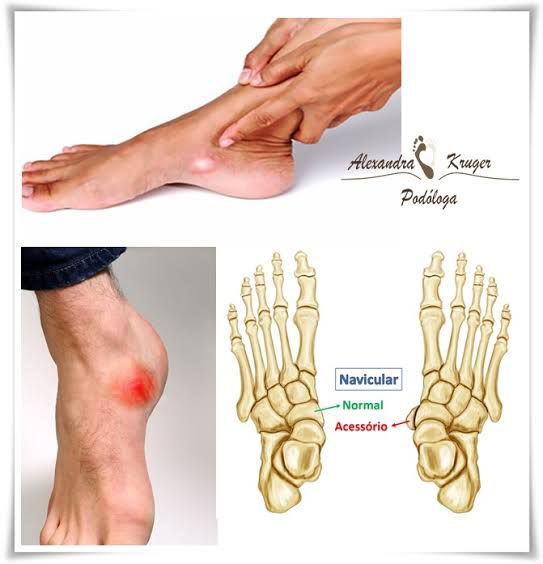

Medicina Free FullText Is the Small Ossicle of Type 1 Accessory Mallory Weiss Navicular This syndrome is distinct from. 1 the definite cause is still unknown. 1 its prevalence seems to be rare with regional variations in frequency. Mallory Weiss Navicular.